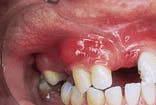

Case 4

Periodontal Abscess

1. Identify the treatment of choice for a periodontal abscess.

e. antimicrobial rinses

2. Identify the typical appearance of the periodontal abscess.

e. none of the above

3. Identify the symptoms associated with the periodontal abscess.

4. Identify the true statement concerning the periodontal abscess.

e. diagnosis is based on a biopsy

CASE 4: 1 = b; 2 = b; 3 = d; 4 = a